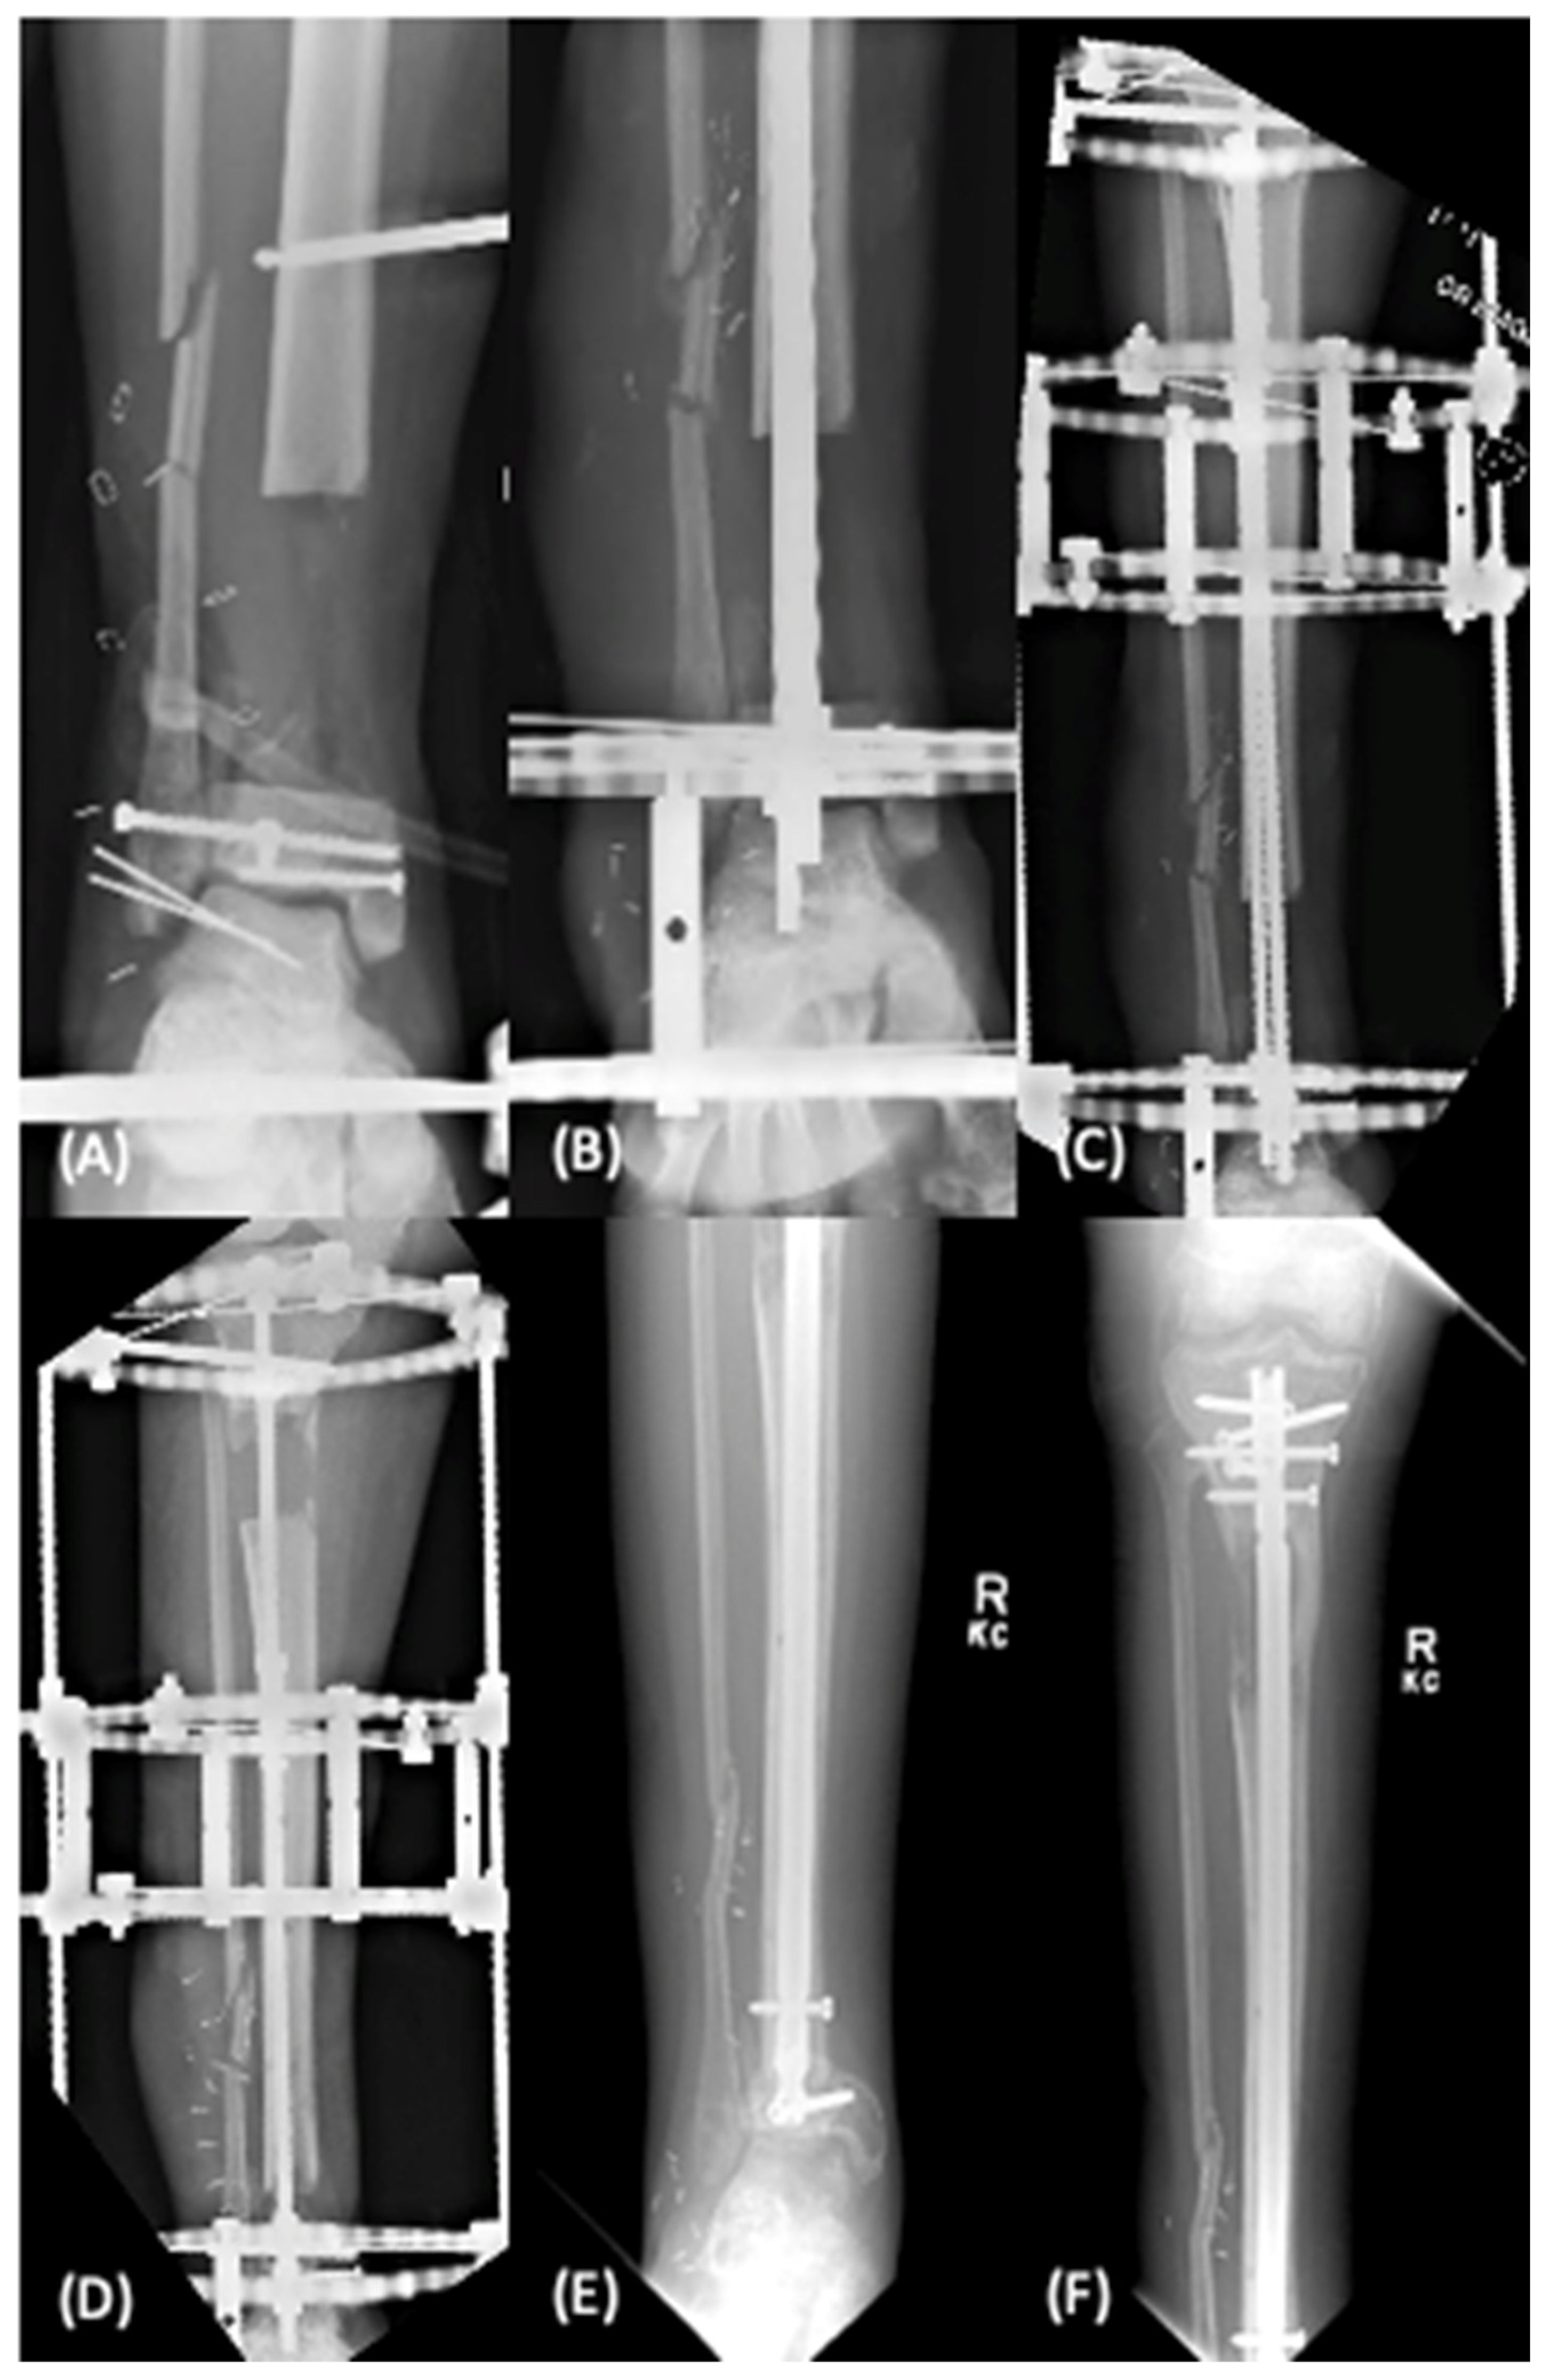

2.1.2. Distraction Osteogenesis